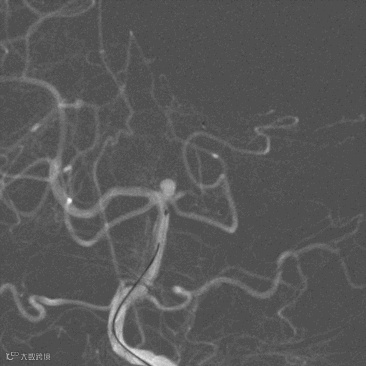

选择合适工作角度,路图下,顺Synchro14微导丝将SL-10支架微导管送至左侧大脑后动脉P2段(图6),将Echelon-10栓塞微导管送至动脉瘤瘤腔内(图7)。

图6

图7